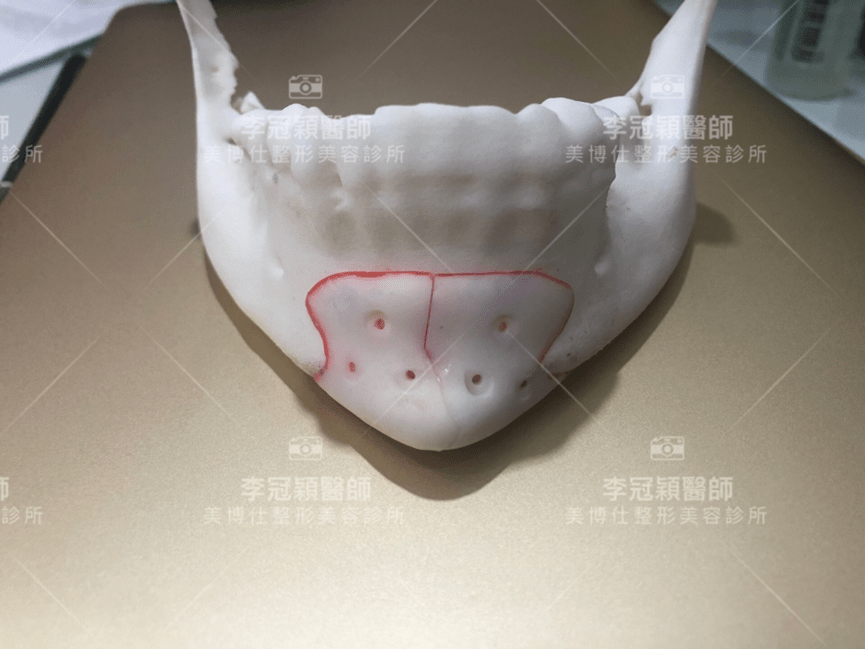

下圖:不對稱下巴骨架,透過列印技術可以做出調整下巴歪斜的假體組合。

歪斜下巴調整性假體設計

下圖範例:歪斜不對稱下巴經3D導航客製化導航矯正性假體

(下圖)3D模擬後工程師版的設計下巴假體的外型。

經過李醫師醫師對客戶外型的判斷,修改工程師的設計,建議更改後的假體模型(下圖)

(上圖)經過李醫師醫師對客戶外型的判斷,修改工程師的設計,建議更改後的假體模型。所以嘍,醫師的美感與專業度必須要做判斷,3D列印只是精準工具但是必須有專業醫師的判斷才可以完美!

下圖: 在李醫師確認後完美精準例印